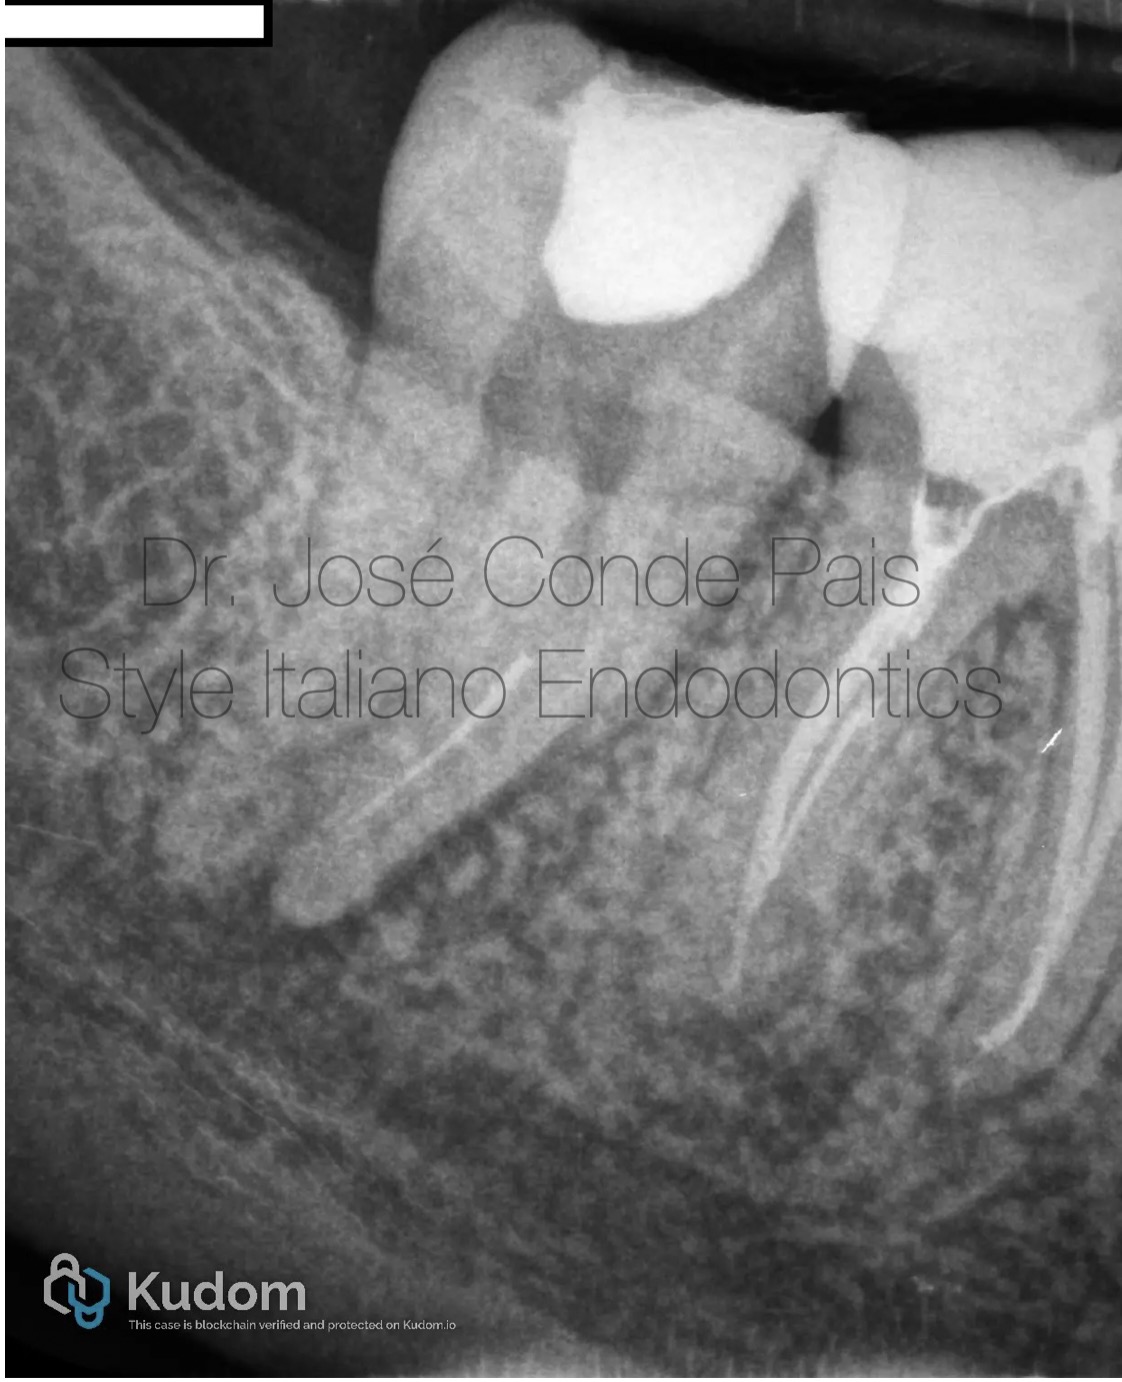

Fig. 2

CBCT Analysis

•Separated instrument beyond apical curvature (MB canal)

•Two independent mesial canals

•Thick buccal cortical plate → surgical approach limited

•Active periapical lesion close to inferior alveolar nerve